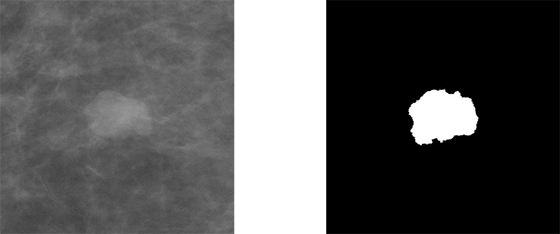

Pentru a înțelege structura rețelei U-Net este necesar să definim datele de intrare (eng. input) și datele de ieșire (eng. output). Așa cum am explicat mai sus, segmentarea presupune selectarea pixelilor care formează regiunea sau obiectul de interes. Acest lucru este reprezentat printr-o mască, o imagine binară, unde pixelii albi descriu obiectul căutat, iar pixelii negrii fundalul. Această imagine este de fapt outputul unei rețele de segmentare. Iar ca input, avem tot o imagine, care conține sau nu obiectul/regiunea de interes.

Figura 3 Exemplu de imagine și mască decupată

Din cauza restricțiilor de memorie și procesare s-a ales decuparea imaginilor și măștilor la dimensiunea de 1024x1024 pixeli, însă ar fi preferabilă utilizarea mamografiilor la dimensiunea lor originală. Decuparea și redimensionarea duce la pierderi de informații și introducerea de artefacte nedorite.